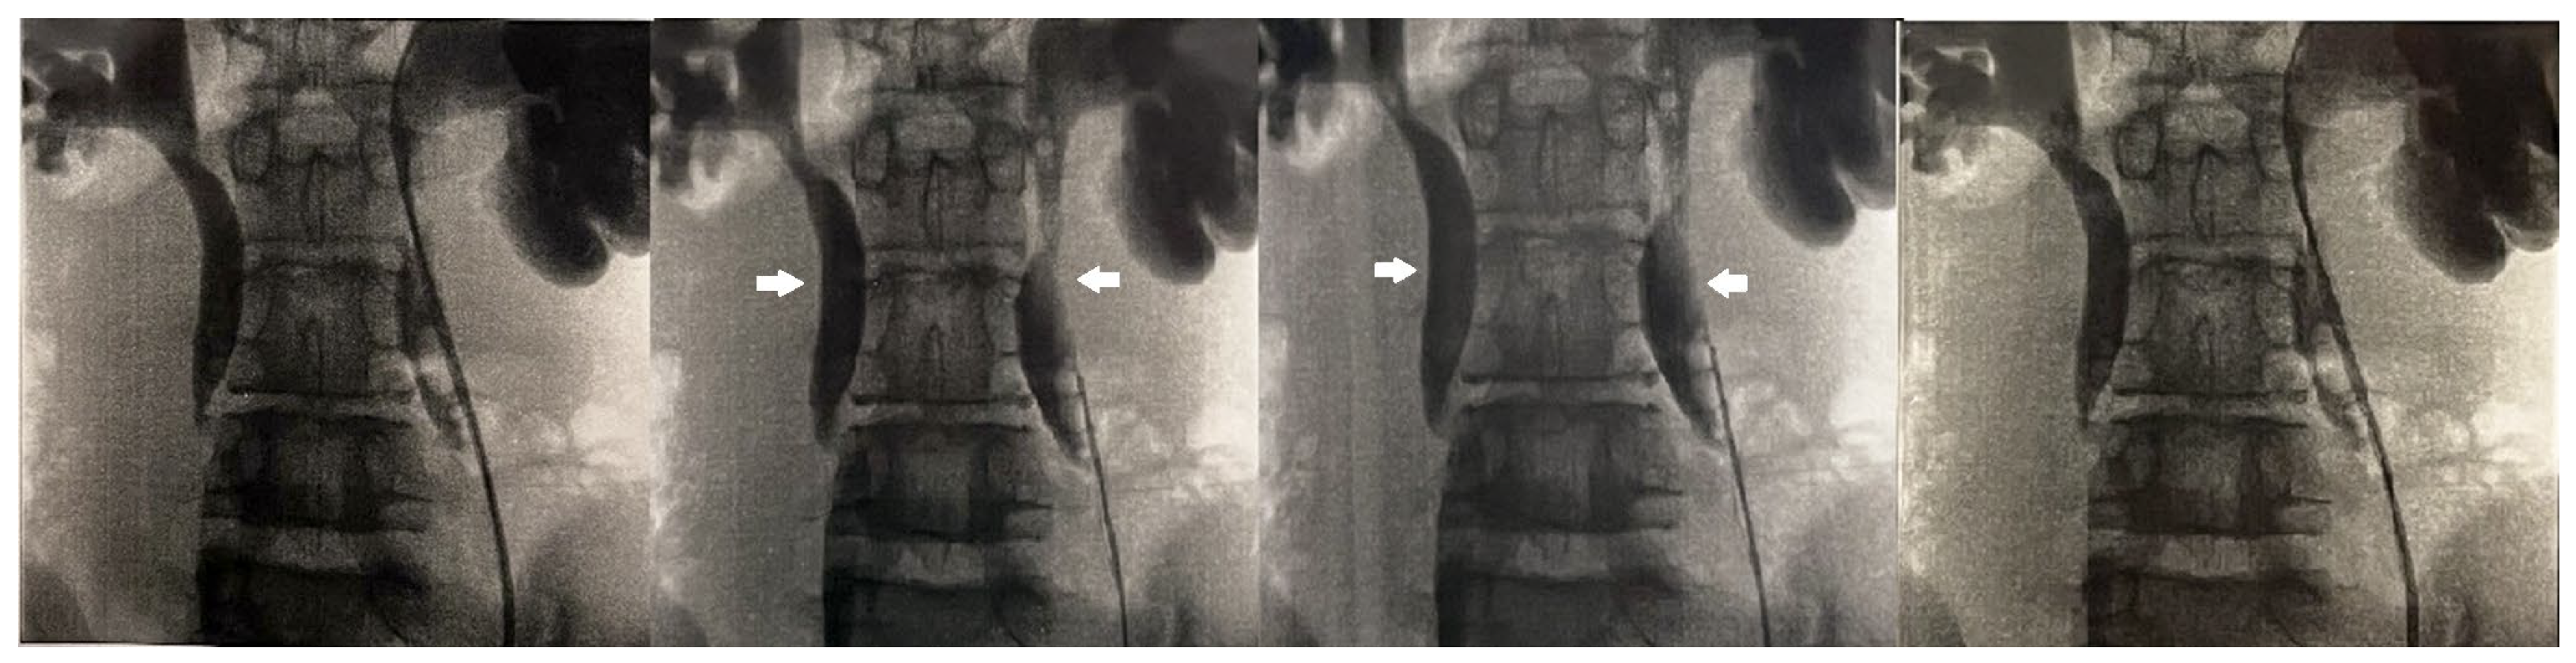

The anterior urethra presented an adequate caliber at urethrocystoscopy using a pediatric 9.5 F scope (KARL STORZ SE & Co., KG, Tuttlingen, Germany). Hypoplastic veru montanum and a blind punctiform orifice, representing the remnant of the resected duplicated urethra, were observed distally to the hypertrophic posterior rim of the bladder neck. The bladder appeared large with slightly trabeculated wall. The right ureteral ostium was narrow and located at the apex of the mound of previous bulking agent implantation, whereas the left ureteral ostium appeared narrow and displaced laterally. After catheterization of both ureteral orifices, retrograde pyelography showed dilatation of both ureters and all calices, which became progressively narrow from the iliac tract to their entry into the bladder, especially on the left side, with delayed contrast washout (Figure 1). Two indwelling 4F ureteral catheters were placed into the left ureter for 8 days to dilate the ureteral orifice. The patient was prescribed urotherapy (alpha-blockers), bladder training with double voiding, and clean intermittent catheterization (CIC) twice a day. No significant improvement was observed at 3-month control, and the patient was poorly compliant with CIC. In the following 8 months, he presented three further episodes of orchiepididymitis, treated with medical therapy. US confirmed persistent bilateral severe hydronephrosis and megaureter, very high bladder capacity (max volume 800 mL), and abnormal PVR (460 mL). To rule out the diagnosis of neurogenic bladder, lumbosacral magnetic resonance imaging (MRI) excluded any intrinsic anomalies of the spinal cord. Urodynamic study revealed a maximum cystometric capacity of 1002 mL, a maximum detrusor pressure of 8.4 cm H2O, and a PVR of 350 mL, consistent with hypotonic and hyporeflexic bladder (Figure 2).

Figure 1.

Retrograde pyelography showing bilateral calyceal and ureteral dilatation (white arrows) and delayed contrast washout.